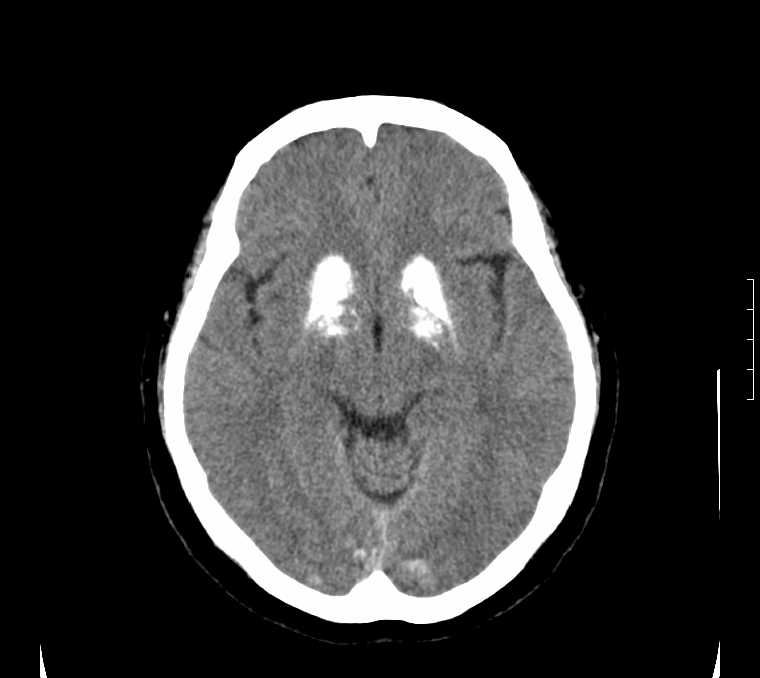

标题: CT24387:看看这例脑部改变!!

老年女性。头晕。

考虑:甲旁减。

fahr病

鉴别于特发性家族性脑血管亚铁钙沉着症(fahr`s病)与甲状旁腺机能低下之间,请结合临床及相关实验室检查。